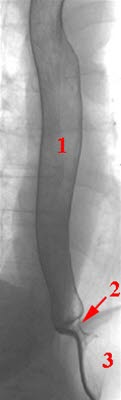

Røntgen av spiserøret og nedre lukkemuskelRøntgen av spiserøret er en kontrastundersøkelse som vanligvis gjøres med bariumholdig væske og eventuelt brusepulver. Barium er et stoff som vises på røntgen. Mens pasienten drikker kontrast følges passasjen ned spiserøret på en skjerm. Tidligere inngikk denne undersøkelsen ofte som en del av undersøkelsen av både spiserør, magesekk og tolvfingertarm, men disse undersøkeslene er i dag stort sett erstattet av endoskopi og CT.

Ved en normal undersøkelse finnes spiserøret glatt, uten svulster og med langsgående slimhinnefolder (se bilde). Det går an å se hvor hovedpulsåren og venstre hovedbronkus klemmer mot spiserøret. Under gjennomlysningen kan peristaltiske bølger observeres, rytmiske sammentrekninger i muskellagene i spiserøret - om de er normale.